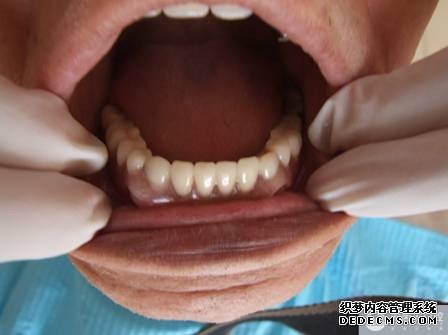

取牙颌模型    义齿加工成型 义齿加工成型    戴入口内 戴入口内    修复完成 修复完成

案例回访:经过活动修复,黄婆婆不仅恢复了部分咀嚼功能,同时还恢复了发音功能。患者非常满意,前不久还派她儿子到我院表示感谢,到目前已修复了2年多,使用情况依然良好。